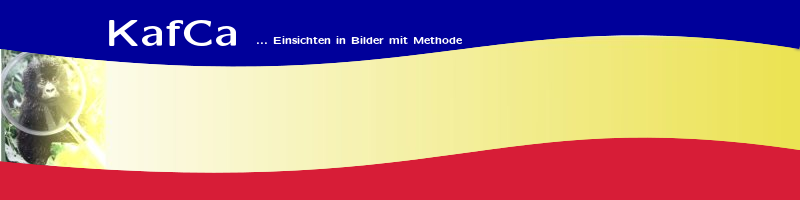

Eingesetzt werden automatische Verfahren zur Segmentierung und Analyse der zweidimensionalen CT-Bilddaten. Sie basieren auf Regeln über die Form und Lage der gesuchten Objekte, deren Grauwertbereich und den Aufnahmeparametern des bildgebenden Verfahrens. Ziel ist die Entwicklung eines allgemeinen Ansatzes zur automatischen Segmentierung anatomischer Objekte aus medizinischen Volumendaten. Daneben werden Methoden zur interaktiven und automatischen Ergebnisklassifikation entwickelt, die in Abhängigkeit von den Anforderungen der nachbearbeitenden Analyseprogramme die aktzeptablen von den nicht-aktzeptablen Segmentierungsergebnissen trennen. |